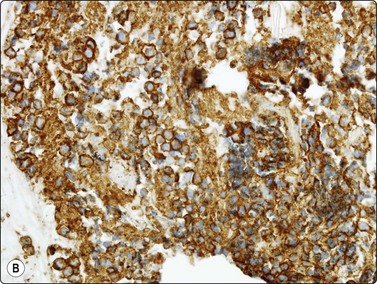

Malignant thymoma (Figs 9.2, 9.7 and 9.8)1-3,18,25,64,70-74

Thymic carcinomas are very uncommon cytologically malignant tumors with a wide variety of morphological appearances including keratinizing and nonkeratinizing squamous, sarcomatoid, anaplastic large cell, basaloid, mucoepidermoid, clear cell and small cell types.1-3 A cytological diagnosis of carcinoma may be made by FNB. Smears are variably cellular and usually dominated by loosely cohesive large malignant cells diagnostic of carcinoma. Most are composed of large tumor cells with solitary clearly malignant nuclei, with or without prominent nucleoli. As expected, their smear appearance resembles the underlying histopathology. Reports of FNB diagnosis of rare subtypes such as basaloid and mucoepidermoid carcinomas area also reported.73,74

image image image

Fig. 9.7 Thymic carcinoma

(A) Disorganized aggregate of pleomorphic malignant cells with macronucleoli; (B) Cell block showing poorly differentiated large cell carcinoma; (C) Staining of tumor cells for CD5 (A, Pap, HP; B, Cell block. H&E, HP; C, cell block, IPOX).